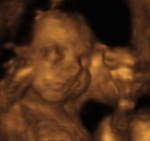

Dopplerultraschall ist ein in der Schwangerschaft angewandtes Verfahren, mit dem die Blutversorgung des ungeborenen Kindes im Mutterleib und auch die kindliche Durchblutung selbst bildlich dargestellt werden können.

Dabei werden an bestimmten Blutgefäßen (z.B. an den zuführenden Gefäßen der Gebärmutter, an der kindlichen Nabelschnur, am kindlichen Gehirn und Herzen) Blutströmungsmuster abgeleitet. Bei Auffälligkeiten kann man Rückschlüsse auf eine Gefährdung des Kindes ziehen und entsprechende Kontrollen durchführen oder Maßnahmen einleiten.